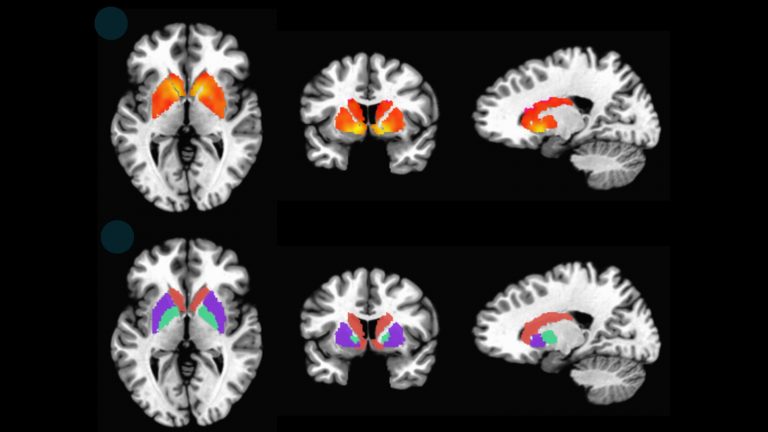

Βρετανοί ερευνητές εφάρμοσαν μια παραλλαγή της μαγνητικής τομογραφίας για να εξετάσουν μια περιοχή του εγκεφάλου που πλήττεται πρώτη από την άνοια.